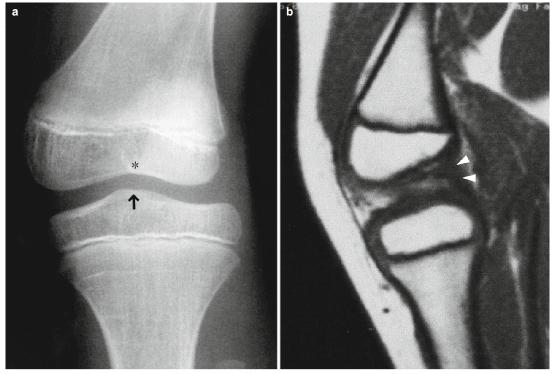

- 髁间隆起可能缺失或变形(图9.20)。

图9.20先天性前交叉韧带缺失。一个8岁的女孩。(a)前后位x光片和(b ) T1WI。股骨外侧髁和髁间间隙(*)发育不全。髁间隆起是单峰的,而不是双峰的(这是正常的)。因此,胫骨变得异常短。MRI显示前交叉韧带缺失,但后交叉韧带存在(箭头)